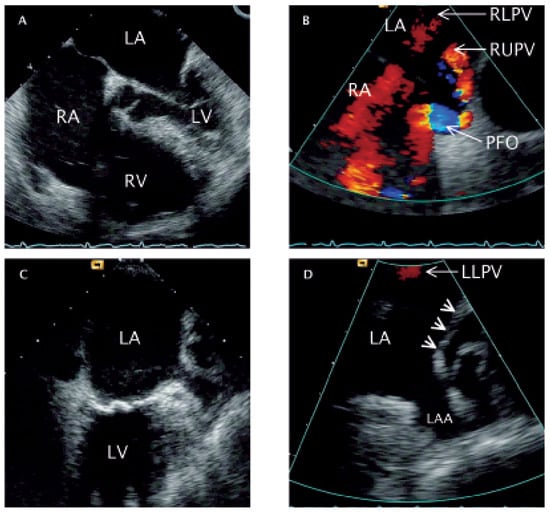

A 68-year-old woman was admitted for rapidly progressive systemic sclerosis. She suffered from exertional dyspnea and decreased exercise tolerance. Pulmonary function testing showed mild restriction with pulmonary fibrosis on high resolution computer tomography (CT). Dilatation of the right ventricle (RV) and right atrium (RA) ( Figure 1 A) with severe tricuspid regurgitation (TR) was detected by transthoracic echocardiography. Transoesophageal echocardiography was performed in search for intra-cardiac shunts, whereby the right upper (RUPV) and right lower pulmonary vein (RLPV) could be depicted ( Figure 1 B). Of the left pulmonary veins, only the left lower (LLPV) could be suspected to drain into the left atrium (LA) ( Figure 1 C,D), and no connection between the left upper pulmonary vein (LUPV) and the LA superior to the left atrial appendage (LAA) (arrowheads on Figure 1 D) could be imaged. Additionally, a large patent foramen ovale with spontaneous right-to-left shunt was found (PFO) ( Figure 1 B). Using angiographic CT, false drainage of the left upper pulmonary vein (LUPV) ( Figure 2 A,B) via the brachiocephalic vein into the superior vena cava could be shown. Cardiac catheterisation revealed normal coronary arteries and normal pulmonary artery pressure. In the context of a slight cyanosis (arterial oxygen saturation of 82%), and keeping in mind the possibly relevant function of the PFO as a release valve for the right heart volume overload (false pulmonary vein connection with secondary tricuspid regurgitation), it was closed transcutaneously by a 35 mm Amplatzer device ( Figure 2 C). The patient was dismissed in good clinical condition.

Figure 1. Transoesophageal echocardiography. A Four-chamber-view obtained at 0° rotation depicting right heart dilatation. B Longitudinal (90°) colour Doppler view of the two atria (caudal: left side of the image; cranial: right side of the image) showing correct drainage of the RUPV and RLPV as red flow velocity signals. In addition, a blue/turbulent flow velocity signal (right-left-shunt) is depictedat the site of the PFO. C Longitudinal (90°) two-chamber-view (anterior: right side of the image) with an enlarged coronary sinus (posterior: left side of the image). D Colour Doppler close-up image of panel C showing the LAA and the absence of a structural opening for the drainage of the LUPV (arrow heads). LLPV: flow velocity signal of the left lower pulmonary vein. RA = right atrium; RV = right ventricle; LA = left atrium; LV = left ventricle; RUPV = right upper pulmonary vein; RLPV =right lower pulmonary vein; PFO = patent foramen ovale; LAA = left atrial appendage; LLPV = left lower pulmonary vein; LUPV = left upper pulmonary vein.